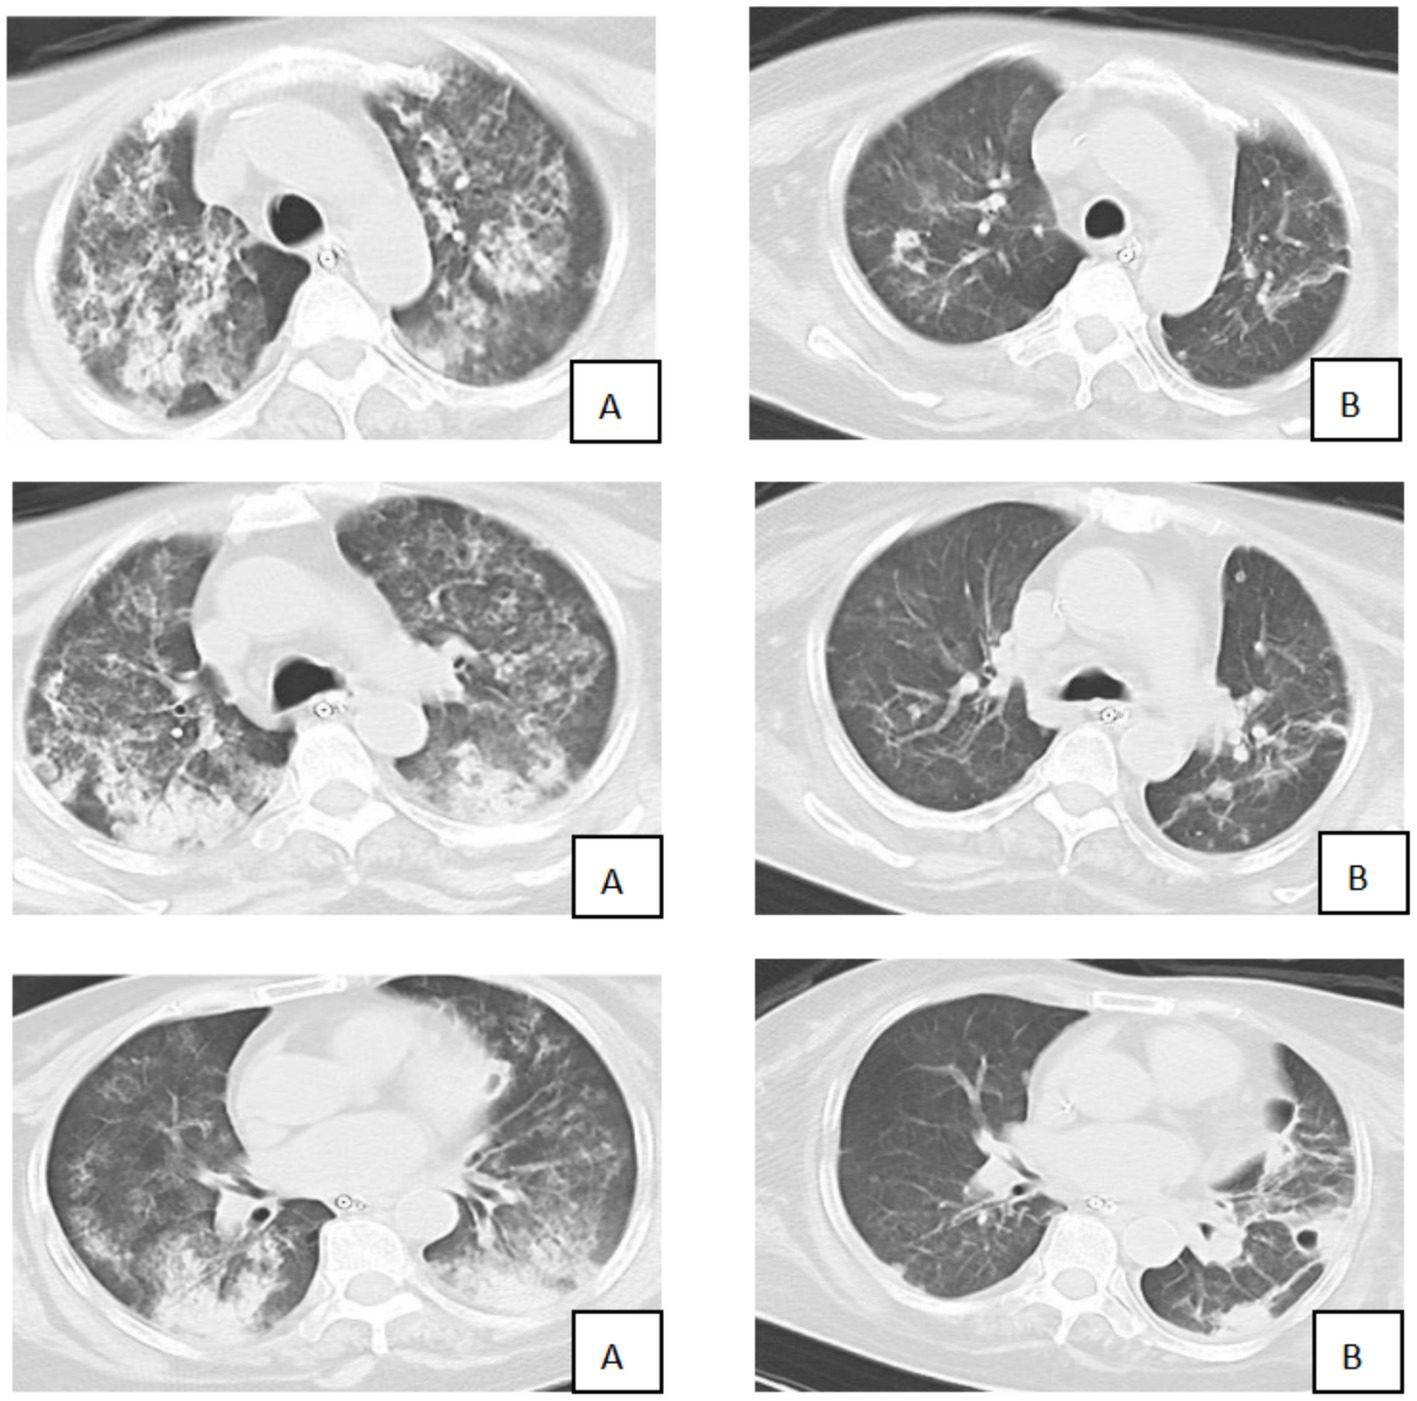

A 57-year-old female farmer was admitted to our hospital with a 3-day history of fever, fatigue, myalgia, and headache. The patient denied recent travel outside the local area but reported frequent work in rice paddy fields. On admission, the patient was febrile, with a body temperature of 39.5 °C, a heart rate of 110 beats per minute, a respiratory rate of 30 breaths per minute, and a blood pressure of 100/60 mmHg. Physical examination revealed scattered rales on the auscultation of both lungs and mild jaundice. Laboratory investigations showed leukocytosis (white blood cell count:15 × 10^9/L), thrombocytopenia (platelet count: 80 × 10^9/L), elevated liver enzymes (alanine aminotransferase: 200 U/L, aspartate aminotransferase: 250 U/L), and elevated creatinine (150 μmol/L). C-reactive protein was significantly elevated at 120 mg/L. The myositis-specific antibody panel revealed the presence of anti-Ro-52 and low-titer anti-Mi-2β antibodies. Bedside transthoracic echocardiography revealed impaired left ventricular systolic function (ejection fraction, 36%) and mild-to-moderate tricuspid regurgitation. A chest CT scan was performed and showed diffuse bilateral ground-glass opacities and consolidation, consistent with alveolar hemorrhage and ARDS (Figure 1).

Figure 1

CT scan images are displayed, showing two rows. The left column (A) exhibits lung images with significant abnormalities or opacities. The right column (B) shows lung images with clearer airways and fewer opacities, indicating a healthier appearance.

Figure 1. Comparison of chest CT before and after treatment (A: 1st August; B: 8th August).

Clinical course

Over the following days, the patient’s condition gradually improved. The volume of endobronchial bleeding decreased, and the oxygenation index continued to improve. On day 4 of ECMO support, the patient’s lung exudation had decreased compared to before, and oxygenation had begun to improve. On day 8, following a comprehensive assessment of respiratory function, oxygenation status, and overall clinical condition, the decision was made to wean the patient from ECMO. The weaning process was uneventful, and the ECMO circuit was successfully removed. The patient was then gradually weaned off mechanical ventilation over the next 3 days.